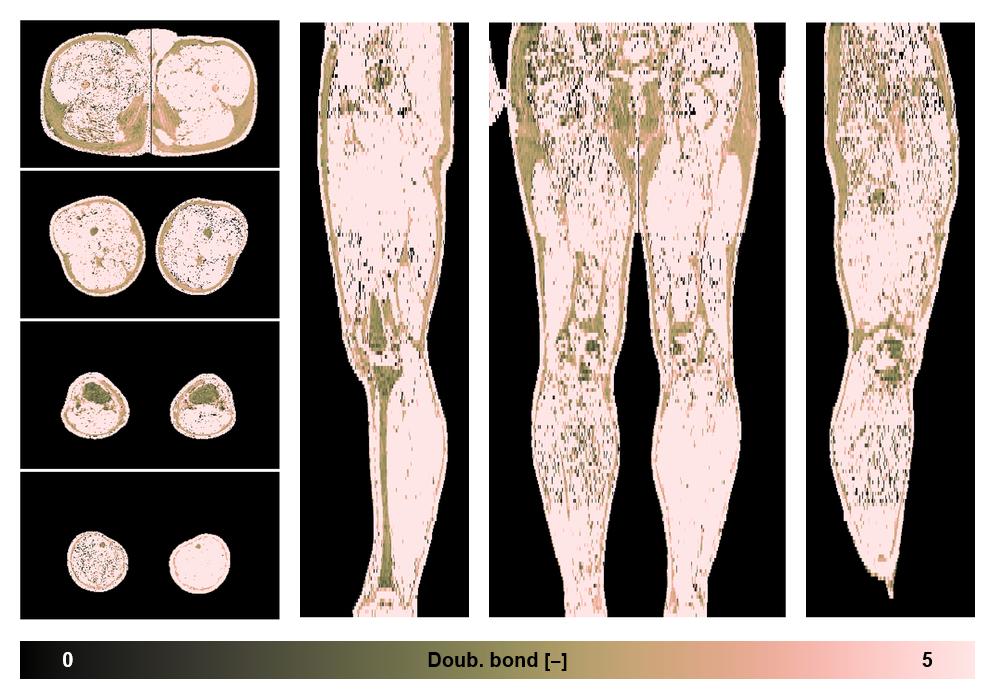

• Number of double bonds in subcutanious fat

Number of double bonds in subcutanious fat.